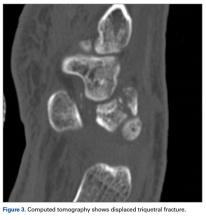

Later, however, the hand surgery team evaluated the radiograph as well as computed tomography (CT) scans and found a translunate, transradial, transtriquetral, transtrapezoid perilunate dislocation of the wrist with multiple metacarpal neck fractures ( Figures 1-5 ).The next day, with the patient under general anesthesia, an attempt to reduce the perilunate dislocation by manipulation was unsuccessful. Open reduction and internal fixation (ORIF) were performed through a dorsal approach; the perilunate dislocation was reduced and stabilized with lunocapitate 1.2-mm Kirschner wire (K-wire). The scapholunate and lunotriquetral ligaments were found to be intact, and the significantly displaced triquetral fracture was treated with internal fixation involving 2 minifragment screws ( Figure 6 ).

Our patient’s associated multiple metacarpal neck fractures can be explained by the peculiar double-impact injury with initial axial loading across the hyperextended metacarpophalangeal joint, followed by axial loading across the hyperextended and ulnar-deviated wrist, causing greater arc perilunate fracture-dislocation. The mechanism of lunate injury in this case seems to be longitudinal impaction of the capitate shearing against the volar lunate in the axial plane causing a volar lip fracture (Teisen type I), and this may be accentuated by tension in the volar radiolunate ligament. 6,7 Associated triquetral fracture in perilunate dislocation is well described in the literature. 6 However, the trapezoid fracture in our case implies a very atypical pattern of force transmission with the arc probably passing more distally through the trapezoid laterally and the triquetrum medially.